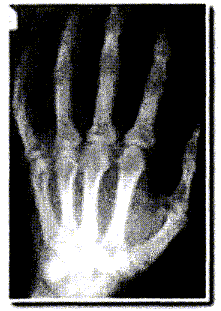

La radiographie enregistre l'image d'un corps traversé par un faisceau de rayons X. Suivant la constitution du corps, les rayons X sont plus ou moins absorbés et le film photographique, placé derrière le corps radiographié, est ainsi plus ou moins impressionné. Le document ci-dessous correspond à la radiographie d'une main. La main placée contre la plaque sensible s'intercale entre la source de rayons X et la plaque.

Lorsque l'absorption est importante, ( une grande partie des rayonx X est arrêté ), peu de rayons atteignent le film : le film est peu impressionné. ( teinte blanche)

Lorsqu'il n'y a aucune absorption ( en dehors de la main par exemple ) , tous les rayons X atteignent le film et l'impressionnent ( teinte noire).

Lorsque l'absorption est faible, ( une petite partie des rayonx X est arrêté ), beaucoup de rayons atteignent le film : le film est assez impressionné. ( teinte grise)

Les os absorbent fortemment les rayons X et apparaissent en blanc.

Les tissus absorbent peu les rayons X et apparaissent en gris.

L'absorption des rayons X est d'autant plus importante que le n° atomique de l'élément chimique est grand.